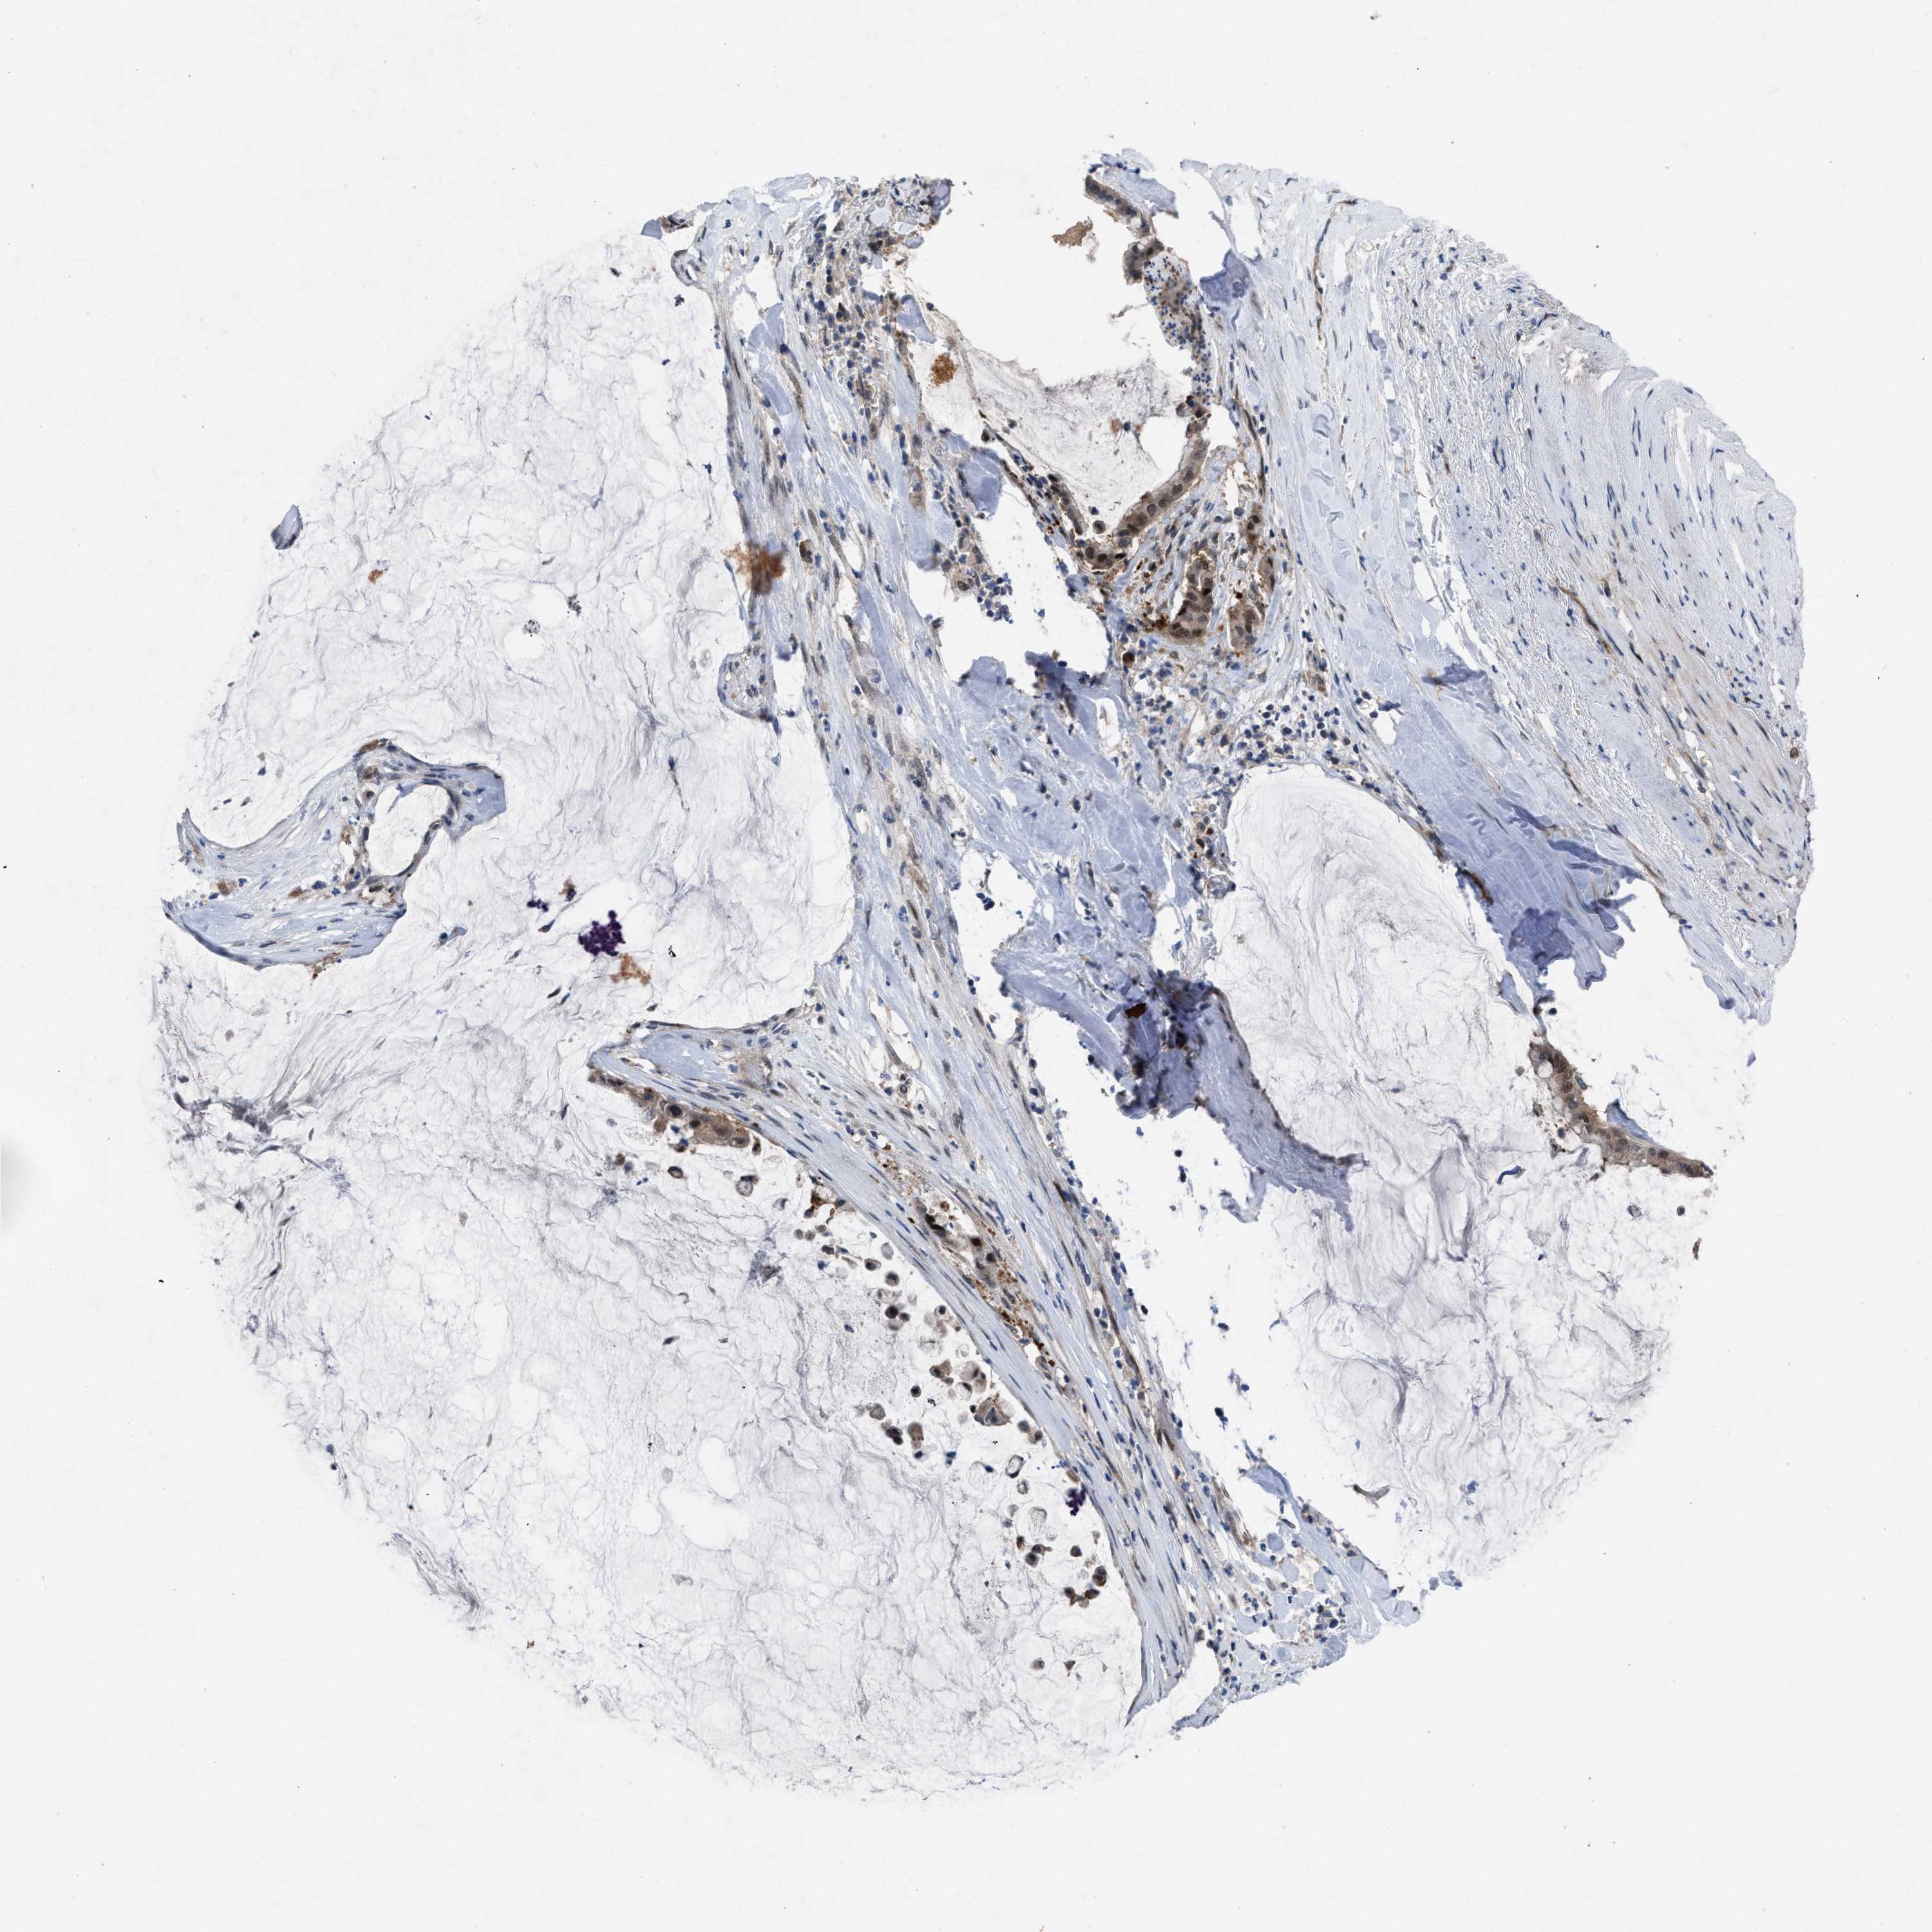

PANCREATIC CANCER - Protein expressioni

A mouse-over function shows sample information and annotation data. Click on an image to view it in a full screen mode. Samples can be filtered based on level of antibody staining by selecting one or several of the following categories: high, medium, low and not detected. The assay and annotation is described here.

Note that samples used for immunohistochemistry by the Human Protein Atlas do not correspond to samples in the TCGA dataset.

Antibody stainingi

Antibody staining in the annotated cell types in the current human tissue is reported as not detected, low, medium, or high, based on conventional immunohistochemistry profiling in selected tissues. This score is based on the combination of the staining intensity and fraction of stained cells.

Each image is clickable and will lead to virtual microscopy that enables deeper exploration of all samples and also displays staining intensity scores, fraction scores and subcellular localization as well as patient and tissue information for each sample.

Antibody HPA019011

Staining

High

Medium

Low

Not detected

Intensity

Strong

Moderate

Weak

Negative

Quantity

>75%

75%-25%

<25%

None

Location

Nuclear

Cytoplasmic/membranous

Cytoplasmic/membranous,nuclear

Adenocarcinoma, NOS